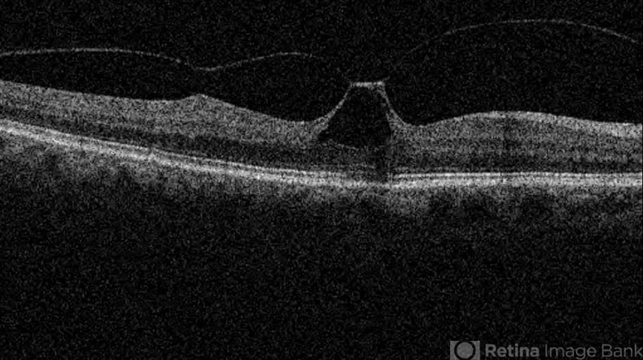

- vitreomacular traction (VMT), optical coherence tomography (OCT)

- Soodabeh Fooladin, Negah Eye Center, Tehran, Iran

- Topcon OCT

- OCT image of the right eye of a 70-year-old woman with visual disturbance due to VMT.